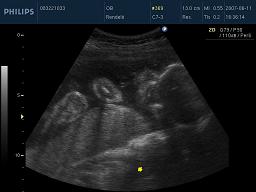

Kicsit sem vagyok elfogult, így nem címzem meg a képet:-))))

Sikerült őket együtt elcsípnem !